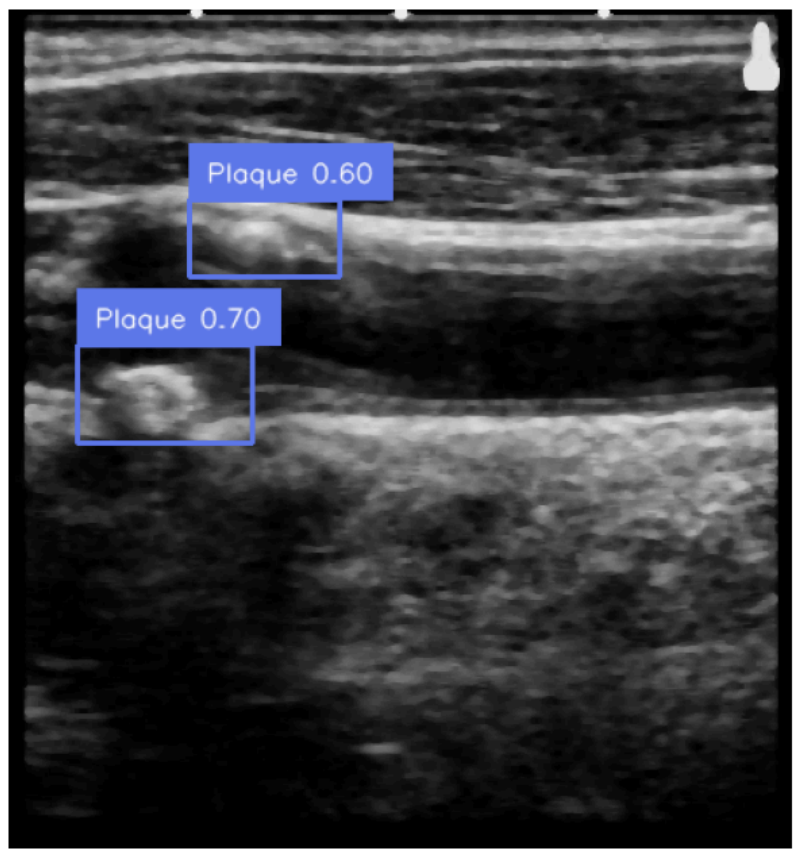

AI-based vascular phenotyping for personalized risk stratification

Using AI on large-scale population-based data, we derive early endophenotypes of vascular disease. These phenotypes serve as subclinical biomarkers and proxy traits in genetic and omics research.